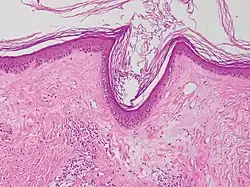

Typische histopathologische Merkmale des Lichen sclerosus sind eine Atrophie der Epidermis mit vakuolärer Degeneration der Keratinozyten (hornbildende Zellen der Epidermis) in der basalen Zellschicht und Sklerose der korrespondierenden Dermis. Der Sklerosezone grenzt zur Tiefe ein zumeist bandartig angeordnetes Entzündungsinfiltrat aus Lymphozyten an. Weitere mögliche Veränderungen sind eine unregelmäßige Akanthose (Verbreiterung des Stratum spinosum der Epidermis) und Hyperkeratose der Epidermis (hypertrophische Form), auf behaarter Haut mit Hyperkeratosen der Haarfollikel.[19]

In extragenitalen Läsionen fehlt häufig die Atrophie und das Entzündungsinfiltrat kann eosinophile Granulozyten enthalten. In der Dermis zeigen sich hier häufiger aufgeweitete kleine Blutgefäße.[20][21] Klinisch bullöse Läsionen gehen mit einem dermalen Ödem bis hin zur subepidermalen Blasenbildung einher.

.jpg) Lichen sclerosus (atrophische Form)

Lichen sclerosus (atrophische Form) -

.jpg) Lichen sclerosus (atrophische Form)

Lichen sclerosus (atrophische Form) -

.jpg) Lichen sclerosus (hypertrophische Form)

Lichen sclerosus (hypertrophische Form) -

.jpg) Lichen sclerosus (hypertrophische Form)

Lichen sclerosus (hypertrophische Form) -

Lichen sclerosus mit follikulärer Hyperkeratose

Lichen sclerosus mit follikulärer Hyperkeratose